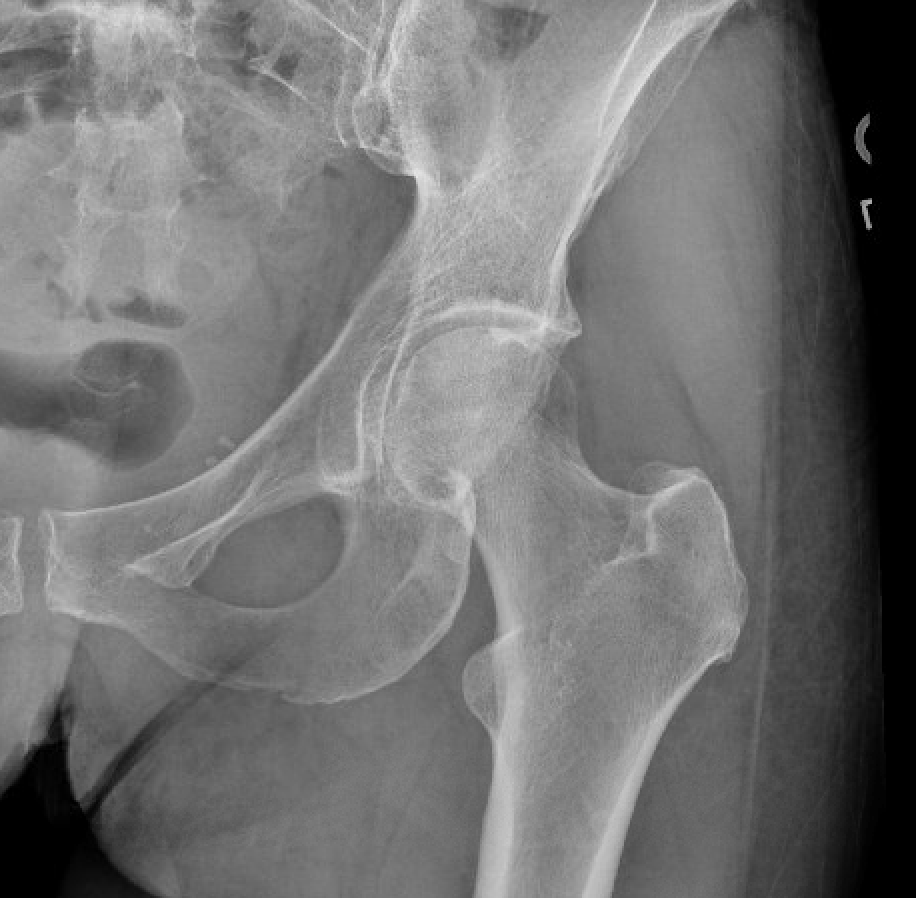

Below is another example of the initial x-rays of a patient who suffered a fall and was unable to walk.